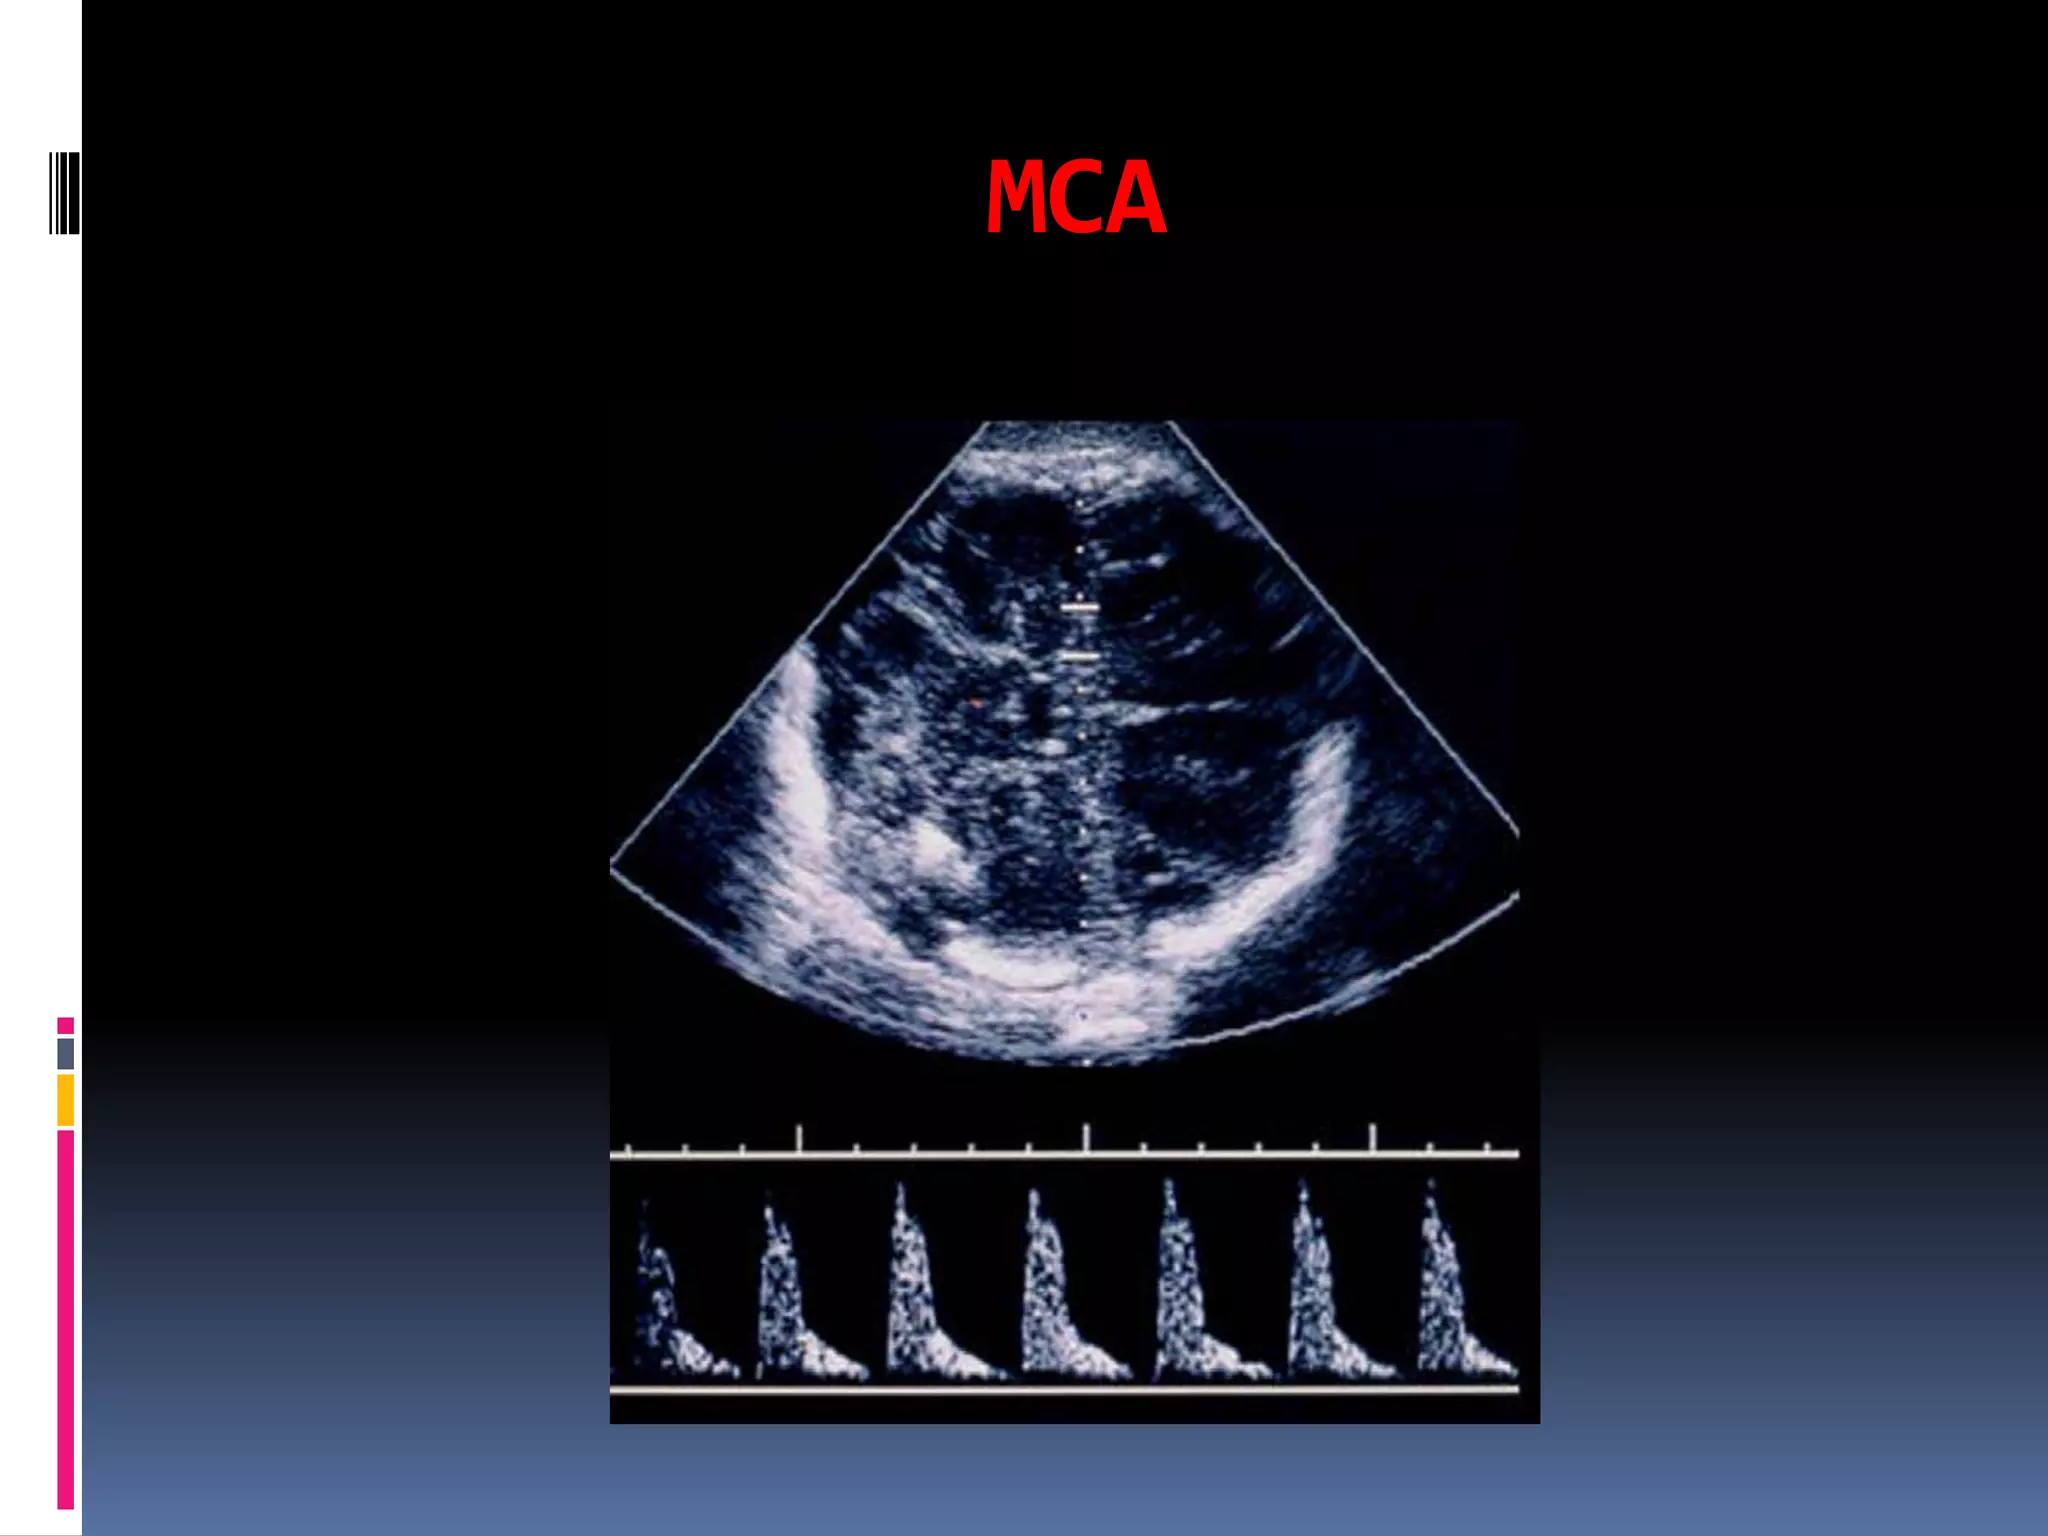

Fetal side; Middle cerebral

circulation

The cerebral circulation is normally a high

impedance circulation with continuous

forward

flow throughout the cardiac cycle.

The middle cerebral artery is the most

accessible

cerebral vessel to ultrasound imaging in the

fetus,

and it carries more than 80% of cerebral blood

flow.

Middle cerebral artery Doppler waveforms,

obtained from the proximal portion of the

vessel, immediately after its origin from the

circle ofWillis, have shown the best

reproducibility.

Late third trimester MCA Doppler spectrum

 At the late third trimester, the PI, RI, and S/D decrease and

the AT increases due to decrease of vascular resistance which

may be attributed to the increase of deoxyribonucleic acid in

the fetal brain (Chandra et al).

34 weeks viable fetus with normal umbilical artery blood flow.